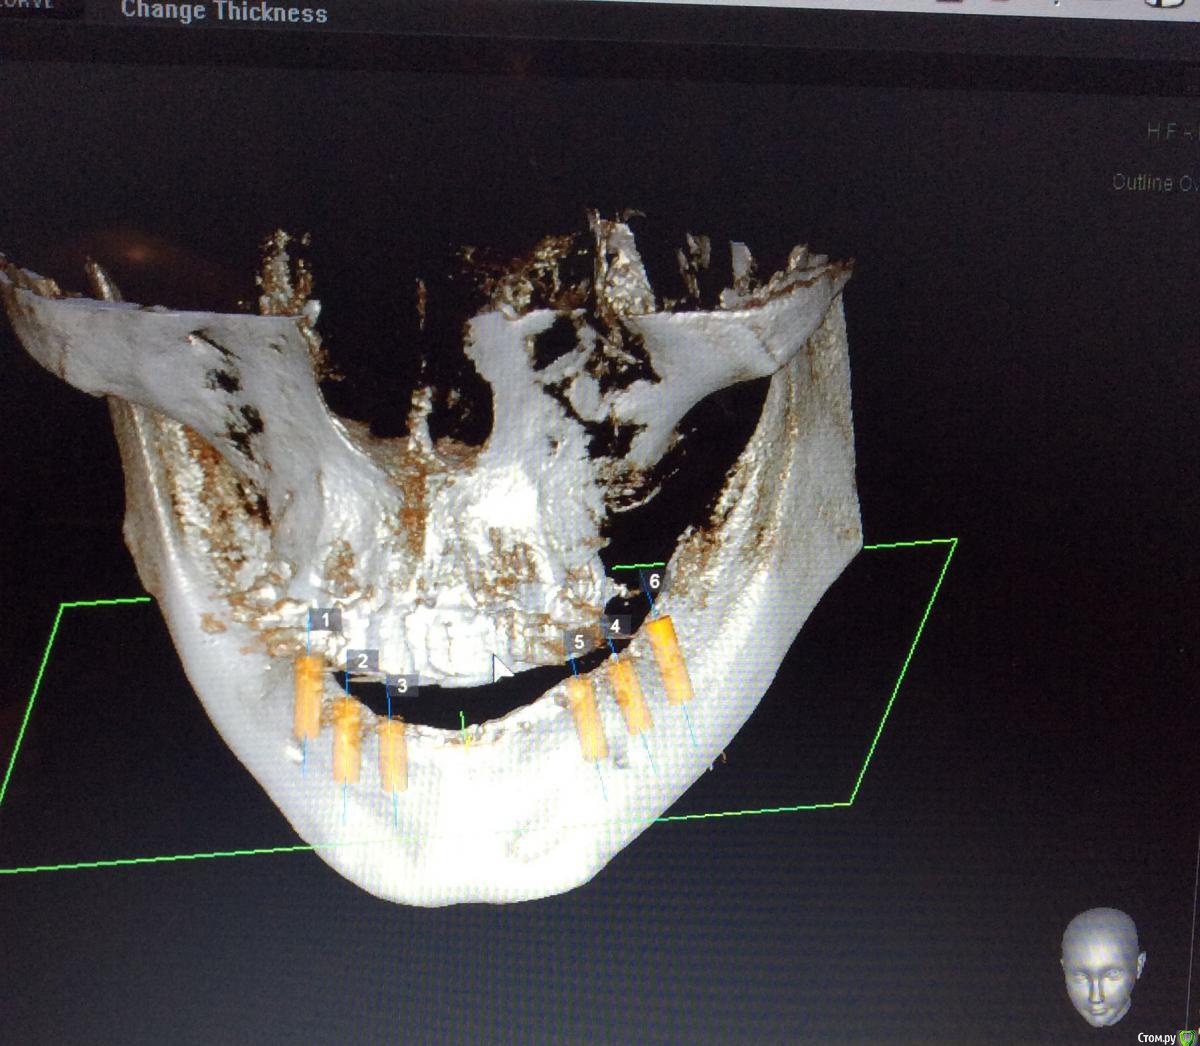

Neilrus Опубликовано 26 мая, 2015 Поделиться Опубликовано 26 мая, 2015 Здравствуйте, подскажите как быть в моей ситауции. Такого объема лечение я еще не выполнял. Беззубая н/ч. Планируем несъемное, "все на 6". Спланировал шаблон по кт на 6 имлантатов, жду его приезда из Москвы. Имплантаты mis m4. 3,8*11,5 и 10.0Планируется так же костная пластика одновременно в районе постановки имплантатов (где-то расщепление, где-то досыпка)Вот отсюда и вопрос, если мы ей пластику делаем, как сдать ей её же временный съемный протез на котором мы ей сейчас прикус зафиксировали? не держать же ее 2 месяца без протеза. У меня вариант в голове только с временными микроимплантатами с шариками Mis, диаметром 3.0 их я смогу и без шаблона поставить.А) Ни разу не делал такой конструкции, так возможно? Б) Двух микроимплантатов в позиции клыков или четверок достаточно? Через какое время можно их нагрузить? В) Ничего что они будут стоять либо между двумя пластиками, либо вообще сквозь ламину (или evolution).Г) Есть какие-нибудь более правильные варианты? Ни один из поставленных имплантатов нагружать не хочу, формики тоже при условии пластики ставить не рискну, опыт еще не тот.Д) профиль челюсти изменится, станет шире, в протезе, если его сдаем, нужно спилить базис немного и сделать перебазировку эластичной пластмассой? Спасибо всем за советы заранее)) сорри если что не так или если повторил тему, не нашел в форуме ответ. Ссылка на комментарий

Neilrus Опубликовано 29 мая, 2015 Автор Поделиться Опубликовано 29 мая, 2015 Сделайте срезы планнинга по каждому имплантату. Там будет понятно.46з45з44з 34з35з36з Может можно воссатновить на двух микроимпл только от клыка до клыка чтобы губа не западала и для сохранения высоты? Ссылка на комментарий